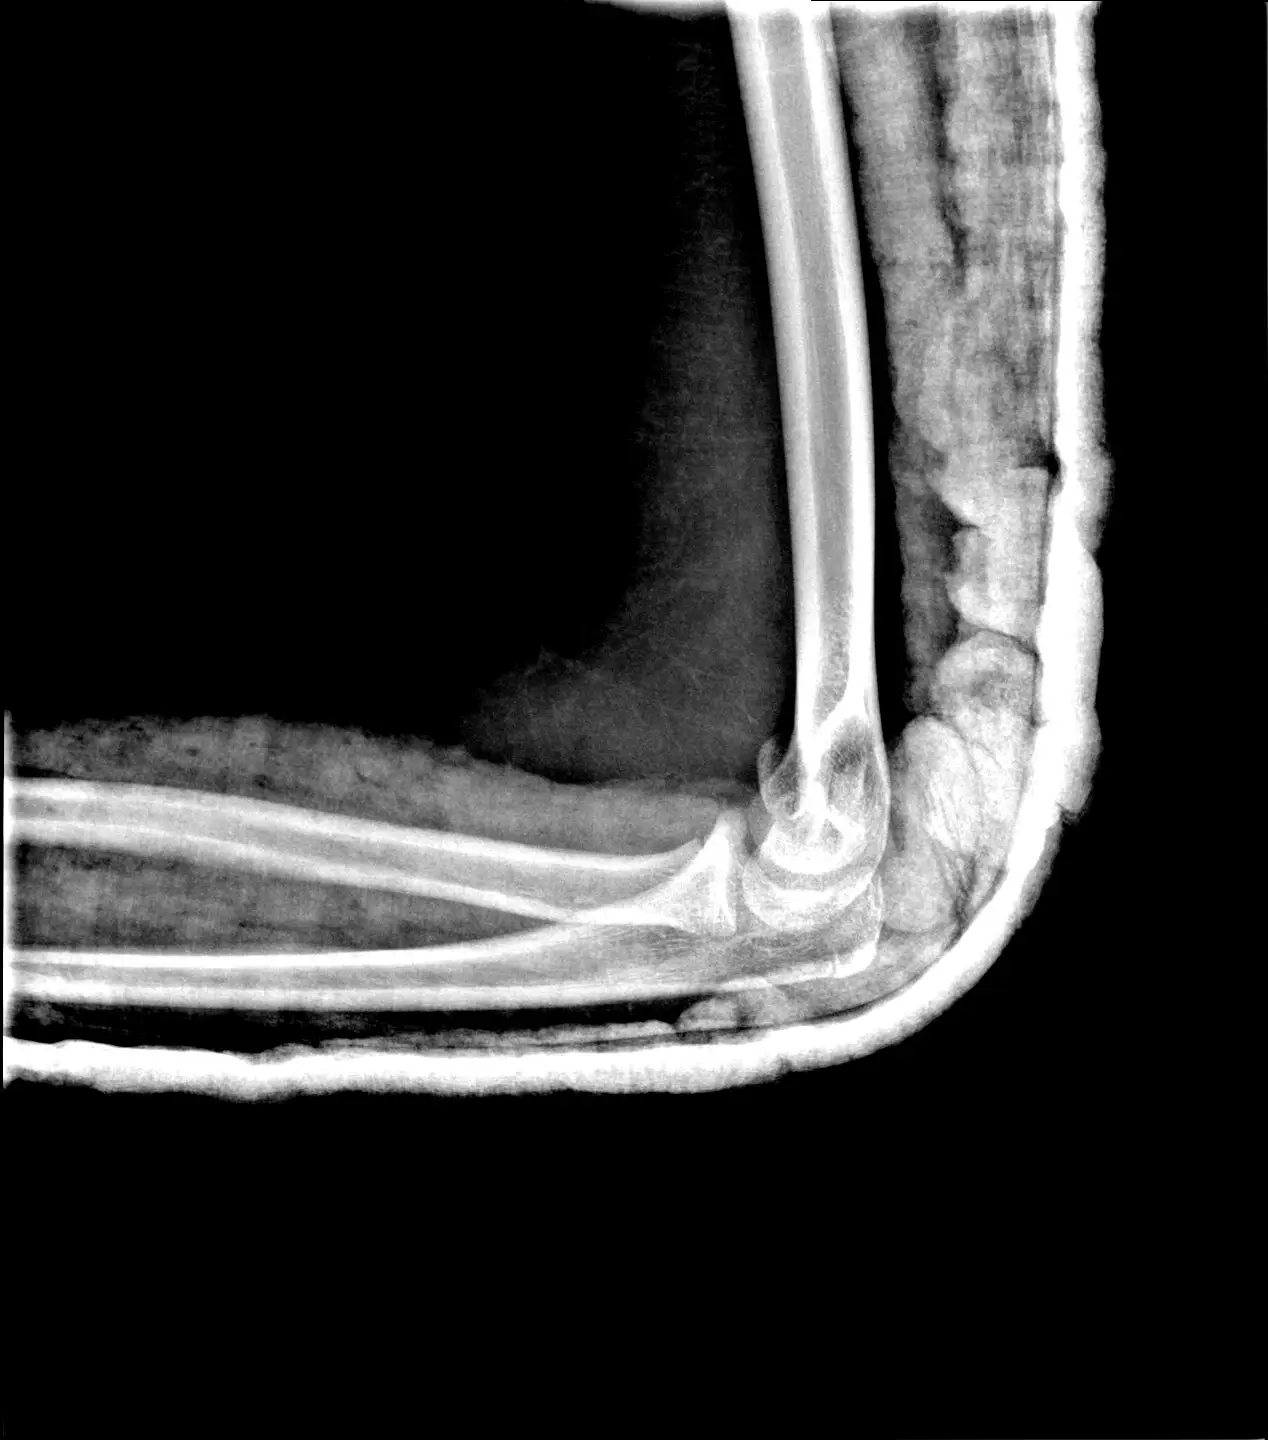

Cierpisz na łokieć tenisisty lub łokieć golfisty? Te powszechne dolegliwości potrafią mocno uprzykrzyć życie i wyłączyć Cię z ulubionych aktywności. Rehabilitacja łokcia w moim będzińskim gabinecie to precyzyjny i skuteczny plan działania. Dzięki dokładnej diagnostyce i terapii celowanej pomagam w stanach takich jak:

- Zapalenie nadkłykcia bocznego (łokieć tenisisty) i przyśrodkowego (łokieć golfisty)

- Bóle przeciążeniowe stawu łokciowego

- Stany pourazowe (złamania, skręcenia)

👉 Nie pozwól, by ból łokcia ograniczał Twoją pasję czy pracę. Dobrze poprowadzona fizjoterapia łokcia tenisisty potrafi przynieść ulgę szybciej, niż myślisz!

Pan Mariusz jest świetnym fizjoterapeutą. Trafiliśmy do Pana Mariusza z 4 letnią córką po poważnym i trudnym złamaniu ręki – wychodząc ze szpitala usłyszeliśmy, że rehabilitacja będzie dla córki kluczowa w powrocie do pełnej sprawności złamanej ręki. Dzięki pomocy, ale przede wszystkim zaangażowaniu i wiedzy Pana Mariusza córka już po 6 wizycie wróciła z ręką do pełnej sprawności. Dziś mija 4 miesiące od złamania i córka nie ma żadnego problemu z funkcjonowaniem ta ręka. Polecam!